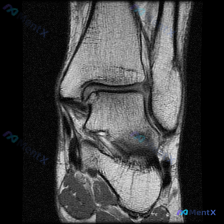

刚整理完这份膝关节MRI的读片思路,这个病例其实挺有代表性,很容易犯锚定错误,分享给大家一起看看。 病例基本影像信息 本次提供的是膝关节MRI矢状位T2加权图像,具体影像学发现如下: 1. 骨骼结构:股骨远端髁前部及滑车无明显骨折,胫骨平台关节面完整无塌陷,髌骨结构未见明显异常;股骨远端周围皮下软组...